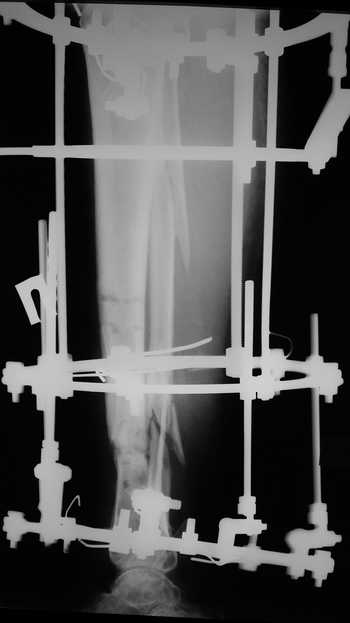

Male 54 years old, diabetic, blind in both eyes, with infected (MRSA) non union distal tibia after fracture 8 month ago. In acute phase treated by ORIF with LCP tibia and fibula. Treatment complicated by infection and after 6 month hardware was removed and treatment continued by cast fixation. You can see malposition of fragments In this stage beginning treated by Ilizarov fixation with use Hexapod system, allows anatomical position of fragments and you see signs of union.

Sorry, I wiil tray now pictures of my case.